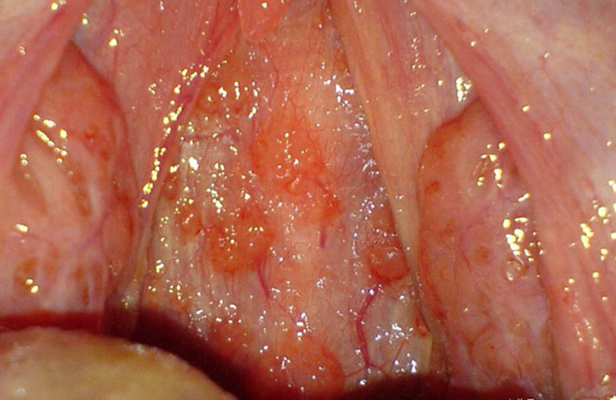

咽喉炎圖片

咽喉潰瘍 (9)